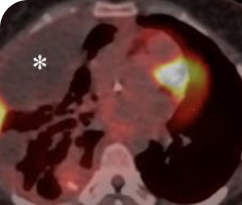

Response in primary and metastatic lesions1

Lung imaging of primary tumors.

SCAN 1: LUNG

SCAN 2: LUNG AND BONE

Images courtesy of Dr Maximilian Hochmair.

Response to VITRAKVI1

- Partial response and symptom improvement confirmed by chest X-rays after <1 month of treatment

- Imaging performed 6 weeks into treatment revealed considerable decrease in the size of both target lesions

- Complete clinical response achieved by 12 months with residual scarring